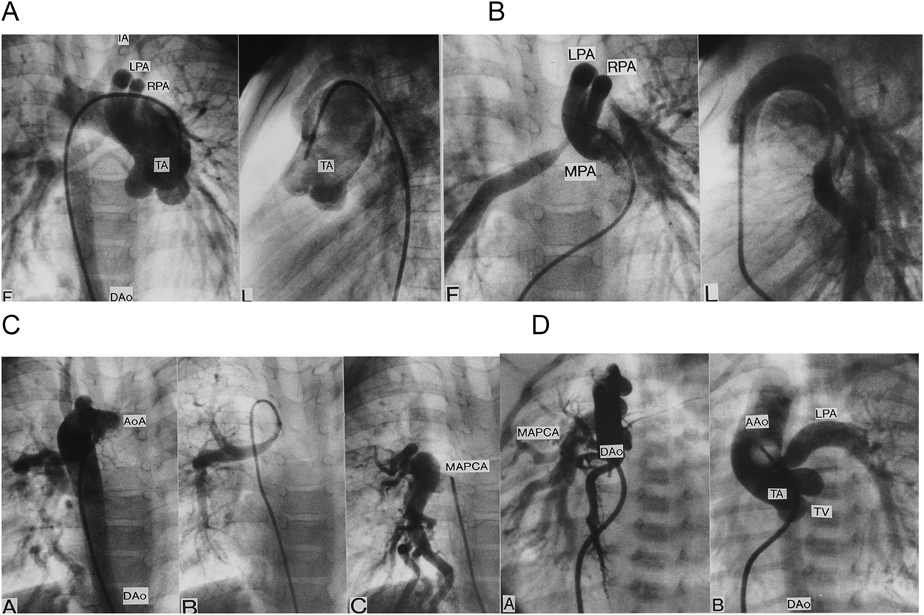

Pediatric Cardiology and Cardiac Surgery 33(1): 3-9 (2017)

Fig. 3 Vascular anomalies associated with chromosome 22q11 deletion and truncus arteriosus (TA)

(A–C) TA, RAA, crossing pulmonary arteries, and MAPCA. (D) TA, RAA, and MAPCA. AAo: ascending aorta, AoA: aortic arch, DAo: descending aorta, LPA: left pulmonary artery, MPA: main pulmonary artery, RPA: right pulmonary artery, TA: truncus arteriosus, TV: truncal valve. Modified and cited with the permission of the authors and publisher from reference 29).

大動脈弓離断は離断部位によりA型,B型,C型の3病型に分類される.A型は大動脈弓の左鎖骨下動脈左で,B型は大動脈弓の左総頸動脈左で,C型は大動脈弓の右総頸動脈左で離断している.本症の大動脈弓離断ではB型になる28).この論文を私が雑誌に投稿したら編集者Anderson教授に人種差があるかもしれないから論文題に〈日本人では〉と入れるよう指示された.不本意ながらそのように加筆して発表したら,この症候群に詳しく,以前から面識のあるローマのMarino教授がローマでも同じだと追加Commentを出してくれた.本症の総動脈幹残遺にはMAPCA,稀な疾患である肺動脈の交差性起始(crossing pulmonary artery)(Fig. 3B)を伴うことがある29).総動脈幹残遺は予後不良のため胎児例の17%に比べて生後例では染色体22q11欠失検索例が少ない.本症で単独に心室中隔欠損を合併することもあり,その場合に大動脈異常(憩室,血管輪)(Fig. 4)を合併することがある30)